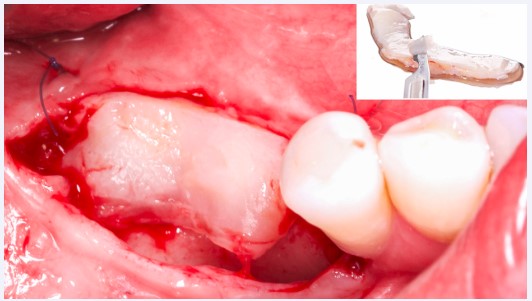

Etapa 1 – Cirurgia de Enxerto de Tecido Conjuntivo Subepitelial

Na primeira fase, foi realizada uma cirurgia para enxerto de tecido conjuntivo visando o ganho de espessura e o aumento

da faixa de mucosa queratinizada. Assim, o enxerto foi coletado da região palatina e fixado com suturas simples (Microsuture). O período pós-operatório evoluiu sem intercorrências, com boa integração tecidual após três meses (Fig. 2).

Figura 2: Enxerto de tecido conjuntivo subepitelial removido do palato e desepitelizado em bancada.